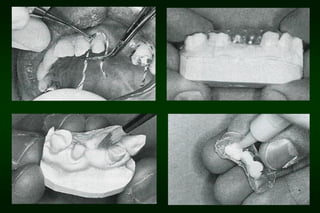

Types of Provisional Restoration II.Customized resin restorations 1. Direct technique a. Direct matrix-assisted • • Elastomeric or alginate impression Vacuum formed plastic template

Types of Provisional Restoration II.Customized resin restorations 1. Direct technique b. Direct custom-carved (block-temporary)